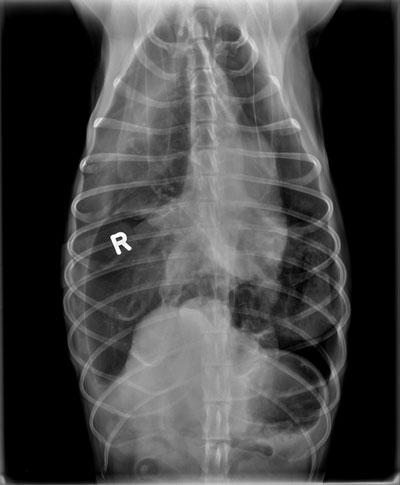

The above radiograph shows severe accumulation of air within the chest cavity of one of the tornado victims due to a damaged lung lobe.

The dogs underwent testing and it was determined that both had suffered trauma to a lung lobe.

“We believe the pressure change during the tornado caused barotrauma to the lung, leading to its rupture, impeding the dogs’ breathing. The difficulty breathing caused a lack of energy,” explains Dugat. “Shortly after the dogs were operated on to remove the damaged tissue, the dogs were reunited with their owners.”